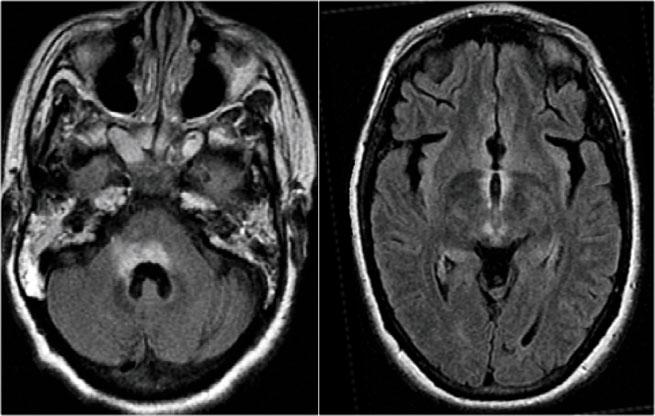

Tổn thương não trong NMO

Trước đây người ta cho rằng não không bị ảnh hưởng trong NMO, nhưng hiện nay chúng ta biết rằng các tổn thương não có thể xảy ra.

Chúng thường khác biệt so với các tổn thương thấy trong MS.

Tại châu Á, 60-80% bệnh nhân NMO có bất thường trên não.

Tại châu Âu, tỷ lệ này chỉ là 25-40%.

Vị trí của các tổn thương não trong NMO chỉ nằm xung quanh các não thất.

Lý do tại sao các tổn thương não này nằm xung quanh các não thất như sau:

Các tự kháng thể NMO IgG nhắm vào các kênh nước Aquaporin-4.

Tương tự như các kênh natri và kali trong tế bào, cũng tồn tại các kênh nước.

Nồng độ cao nhất của các kênh nước Aquaporin-4 được tìm thấy xung quanh các não thất.

Hình ảnh cho thấy tín hiệu bất thường xung quanh não thất ba và sừng trán của các não thất bên.

Vấn đề trở nên phức tạp hơn khi cũng có thể gặp các tổn thương lớn ở thể chai (corpus callosum) ở bệnh nhân NMO, như đã được Nakamura mô tả (6).

Do đó, trong bất kỳ bệnh lý hệ thần kinh trung ương nào có tổn thương thần kinh thị giác và tủy sống, nên thực hiện xét nghiệm NMO-IgG.